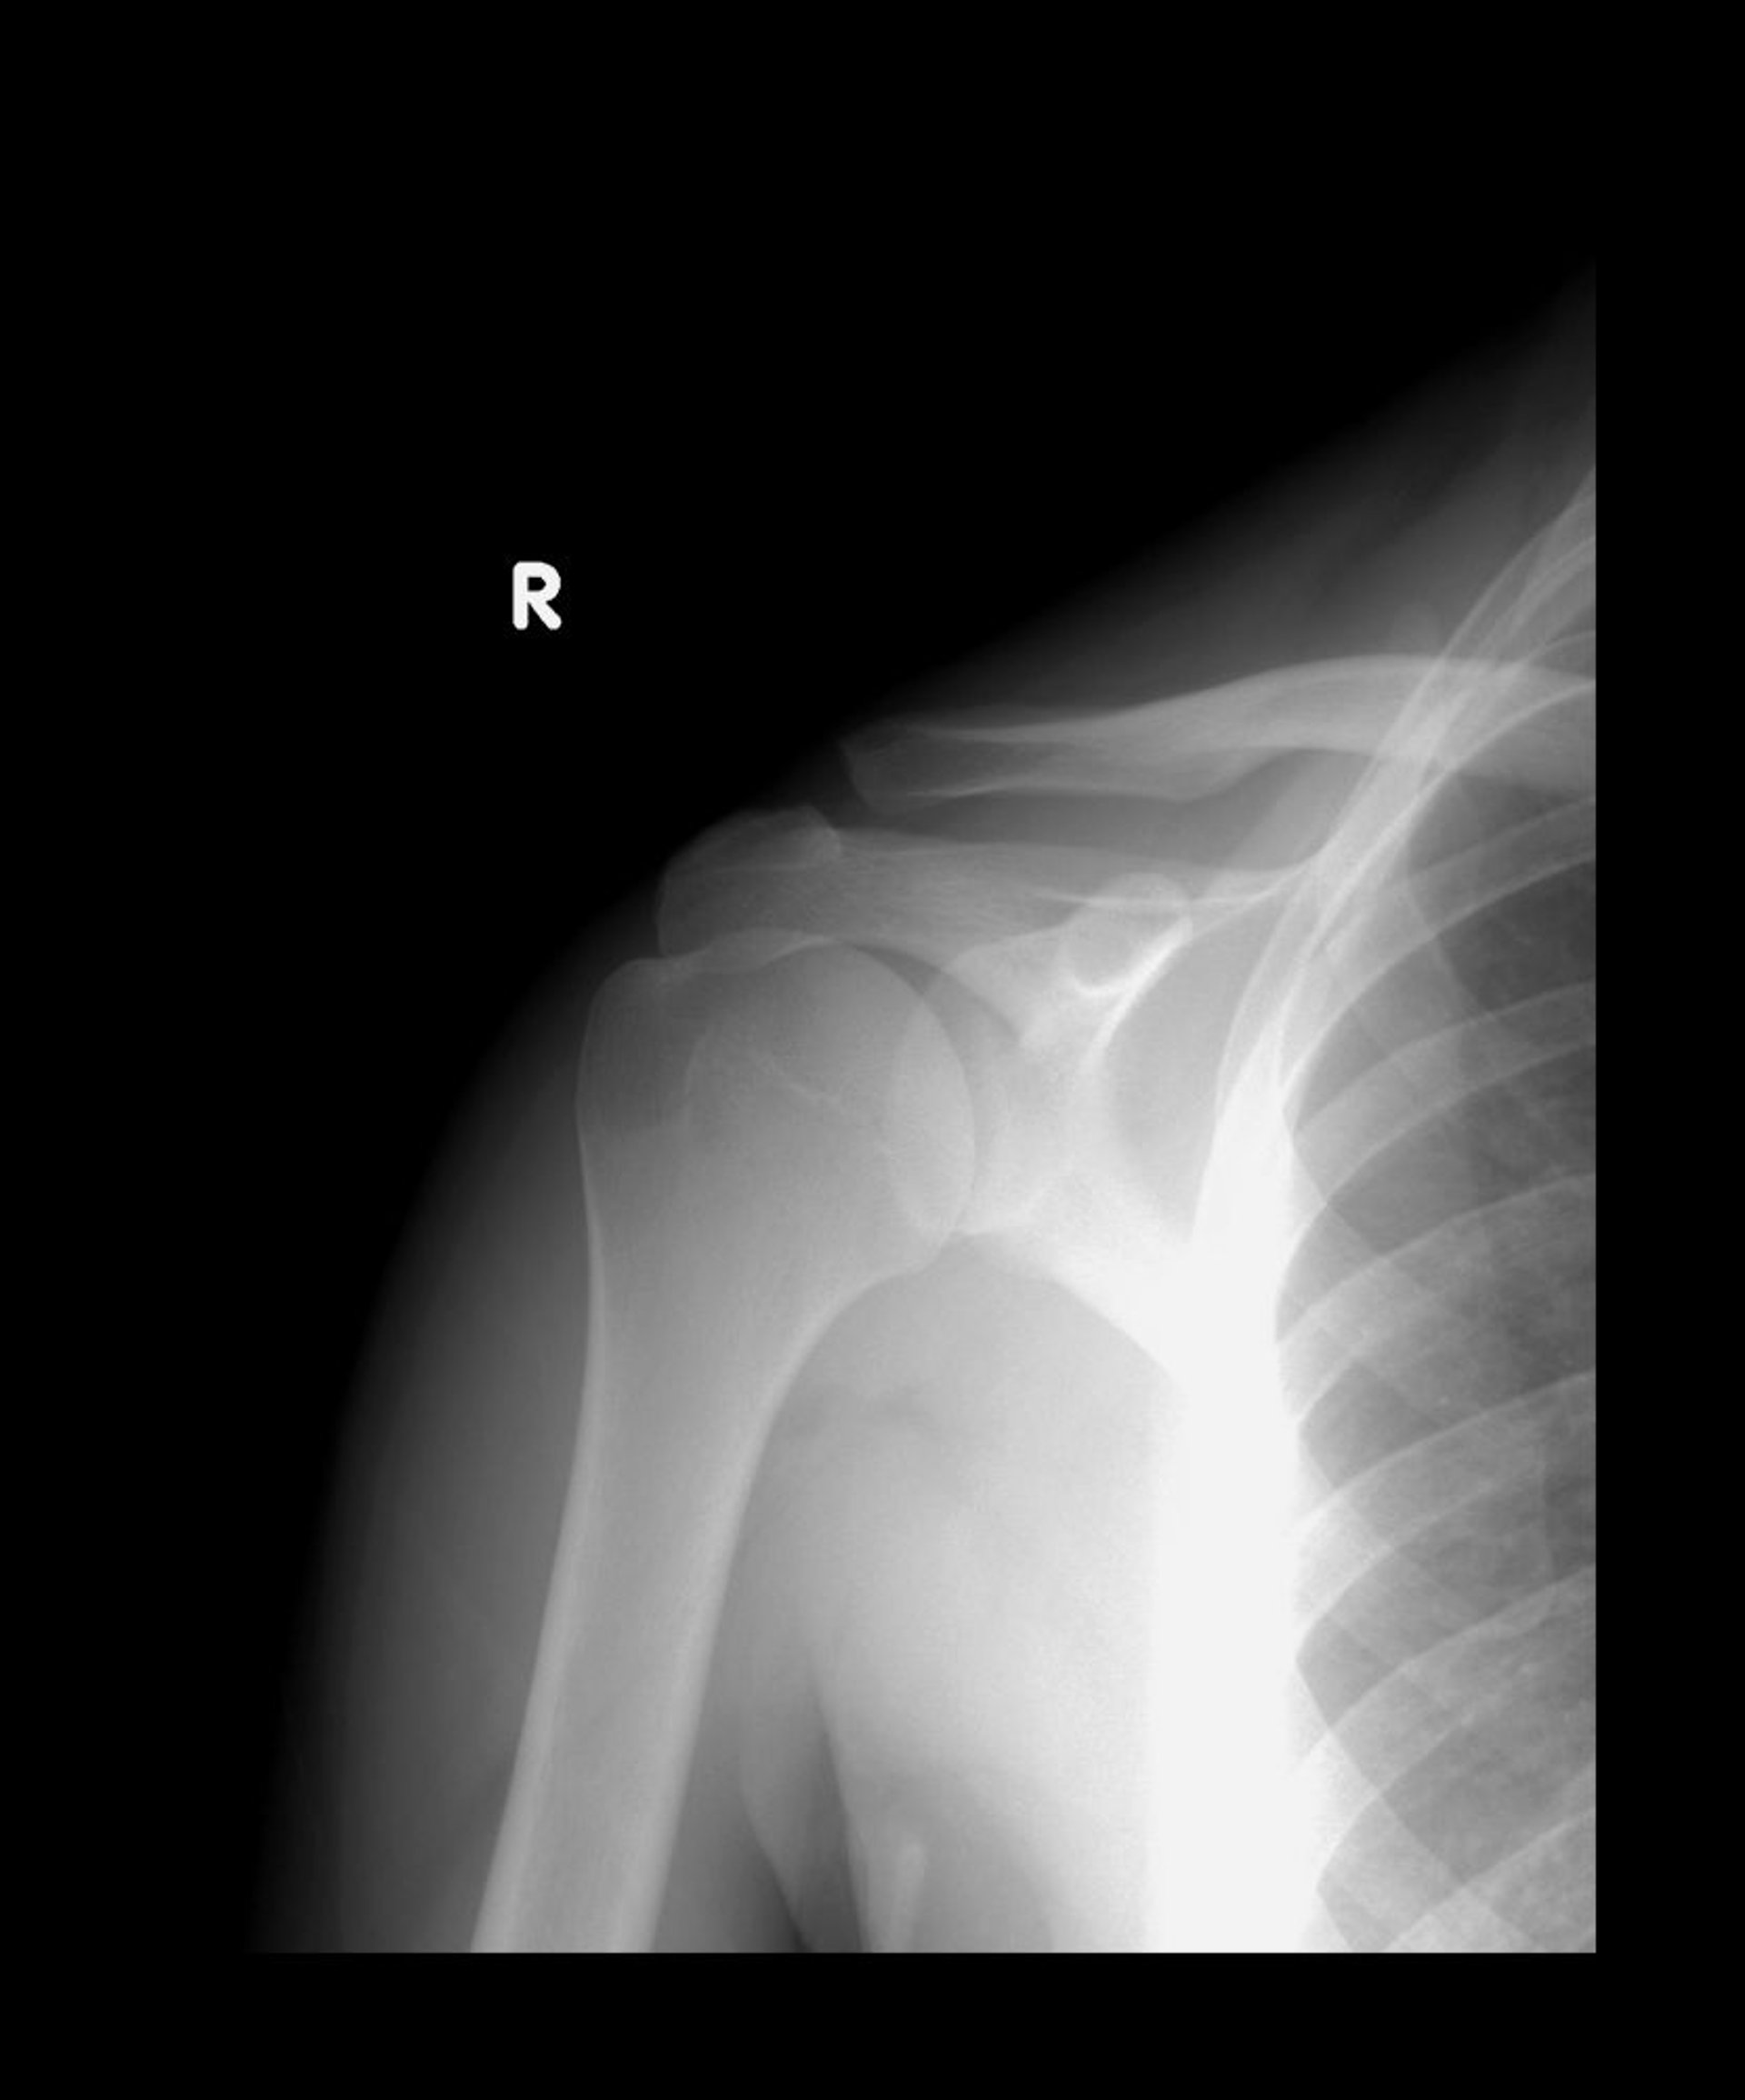

Acromioclavicular Joint Sprain

Normally, the lower ends of the acromion and clavicle align. In this radiograph, the clavicle is displaced upward but the 2 bones still overlap, suggesting a type II subluxation.